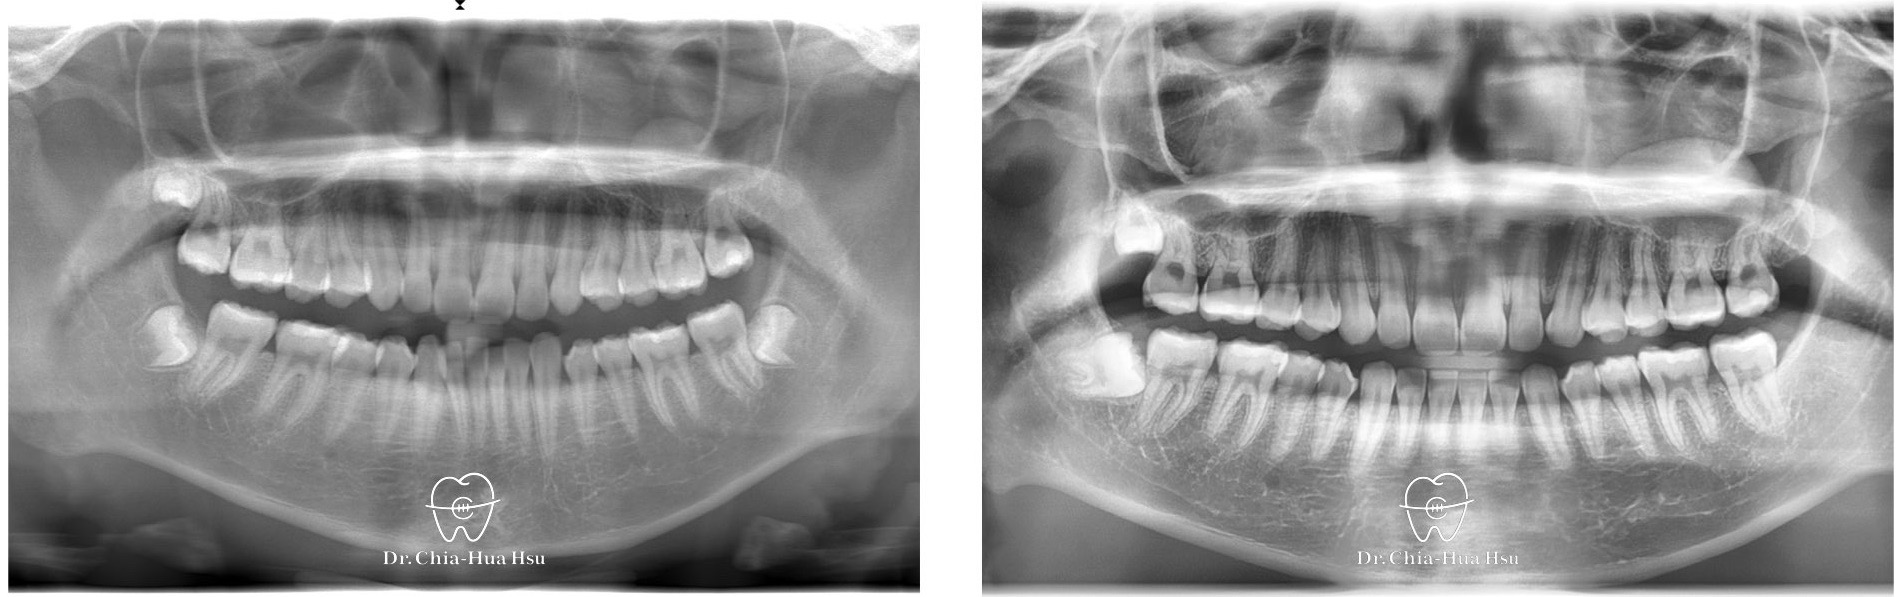

治療前

治療後

• 病患主訴:牙齒凌亂擁擠。

• 問題分析:患者是標準的骨骼一類咬合(Skeletal Class I)伴隨齒列擁擠以及咬合平面傾斜。

• 治療方式:使用傳統金屬矯正器,撐寬牙弓以獲得空間,並搭配二級橡皮筋牽引(Class II elastics)。

• 治療時間:1.5 年。

• 治療結果:齒列排齊,笑容更自信。